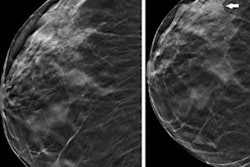

Digital tomosynthesis generates image slices from low-dose projections at different angles, the team explained; it has been established as an effective technique in breast imaging and has begun to be explored for use in orthopedic surgery and musculoskeletal applications. X-ray tomosynthesis may be a "suitable alternative to multidetector [CT] of the appendicular skeleton for trauma or preoperative imaging," eliminating the problem of superimposition of anatomical structures in spinal x-ray imaging, the group wrote.

The team conducted a study that included eight cadavers and used a gantry-free twin robotic scanner to procure lateral conventional x-rays and x-ray tomosynthesis images of the lumbar spine. Five musculoskeletal radiologists assessed image quality between the two techniques, including the extent of any image quality deterioration near scan volume margins.

The study showed that x-ray tomosynthesis offered substantial dose reduction compared to conventional x-ray. Diagnostic image quality was highest using a 30 fps (frames per second) wide-angle tomosynthesis protocol. The team also reported good-to-excellent interrater reliability on x-ray tomosynthesis imaging (range, 0.85 to 0.95, with 1 as reference).